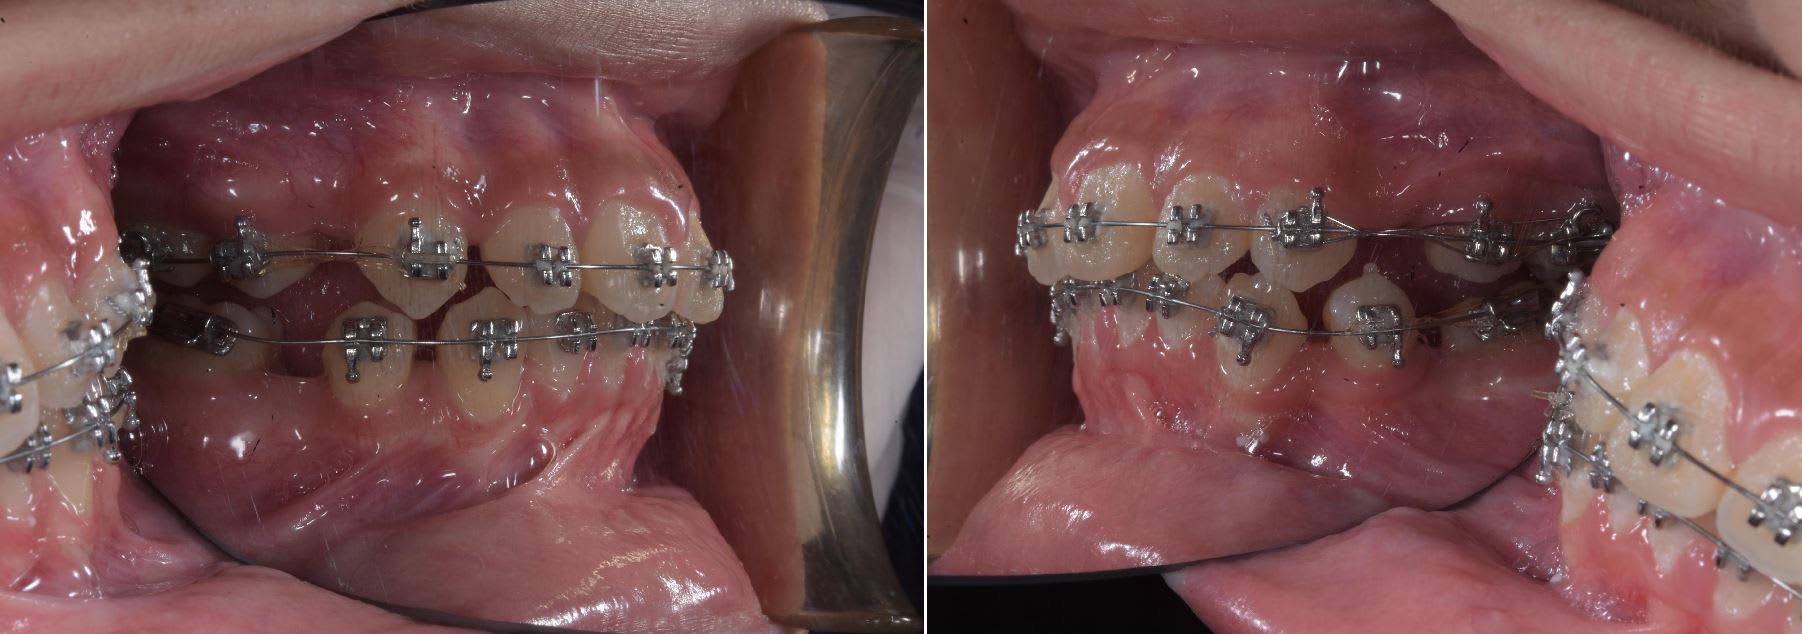

Ici un cas sans extraction une mécanique plus classique avec surélévation est nécessaire. Ici triple cross bite. Des deux coté niveau des pm et la 47 incliné à 45°

Pour la 47 j'ai utilisé une mécanique à la Mulligan pour ceux qui connaisse, une autre alternative aurais était d'utiliser une minivisse.